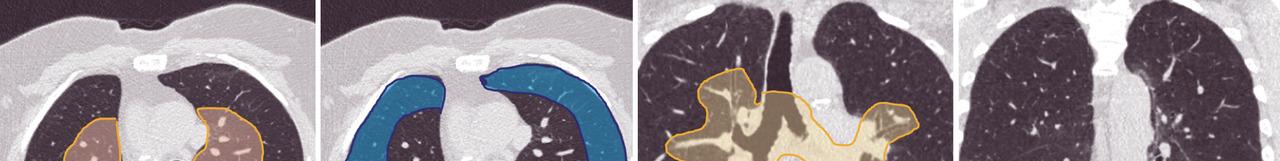

A : zone de distribution centrale, B : zone de distribution périphérique, C. zone de distribution péribronchovasculaire, D : zone de distribution sous-pleurale basale. Lire aussi Article L’apport méconnu des scanners dans l’évaluation de la dénutrition Article Imagerie dans les cancers de l’ovaire Article Web Gonalgie : quand prescrire une imagerie et laquelle ? Article Web La mammographie pour détecter les patientes à risque cardiovasculaire ? Article Douleur thoracique stable : le coroscanner d’abord Article Pneumopathie interstitielle diffuse